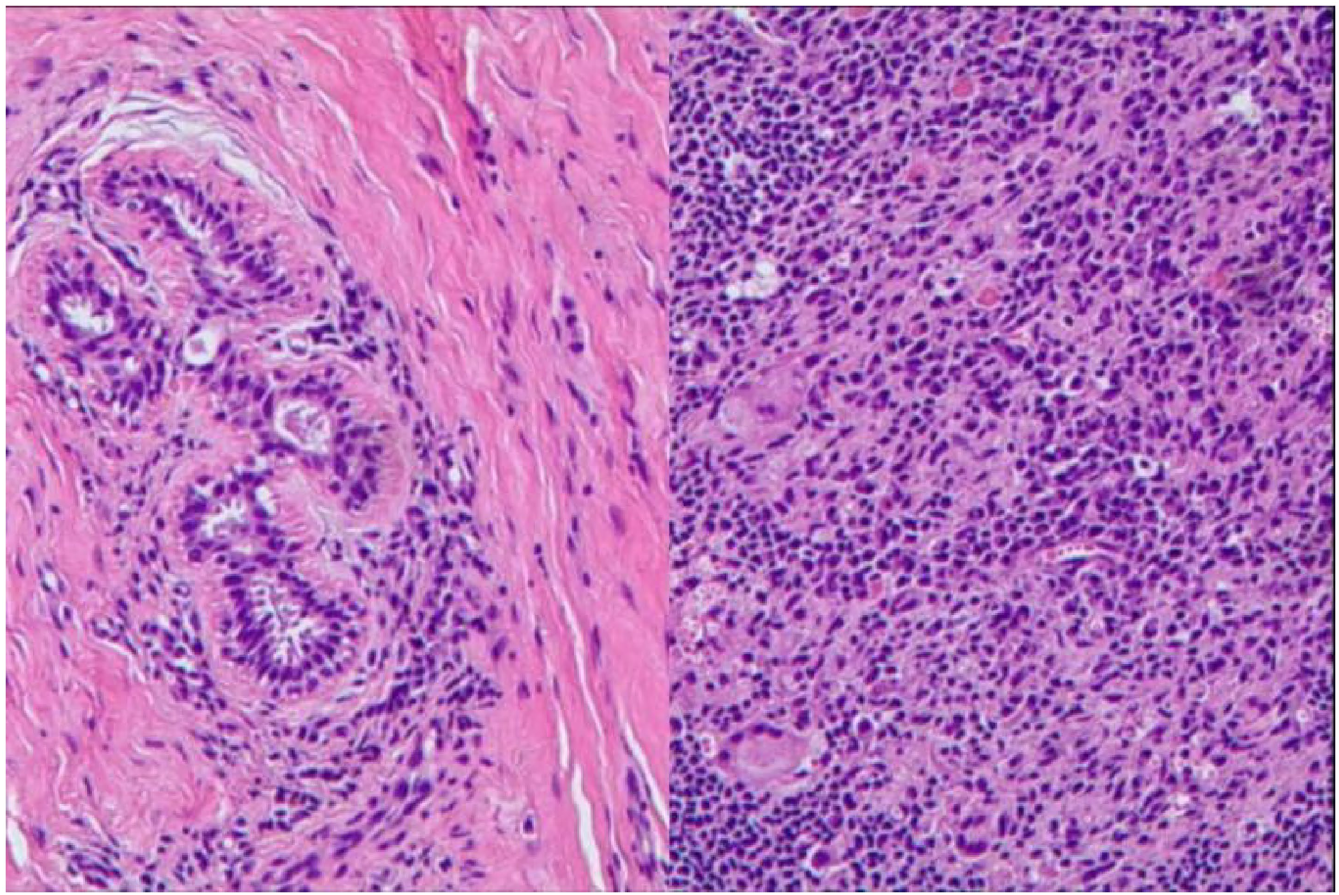

• 镜下病理:乳腺实质内可见浆细胞、中性粒细胞及多核巨细胞密集浸润,符合浆细胞性乳腺炎表现(图 3),无恶性细胞及不典型增生。

图3 切除乳房标本的组织病理学检查